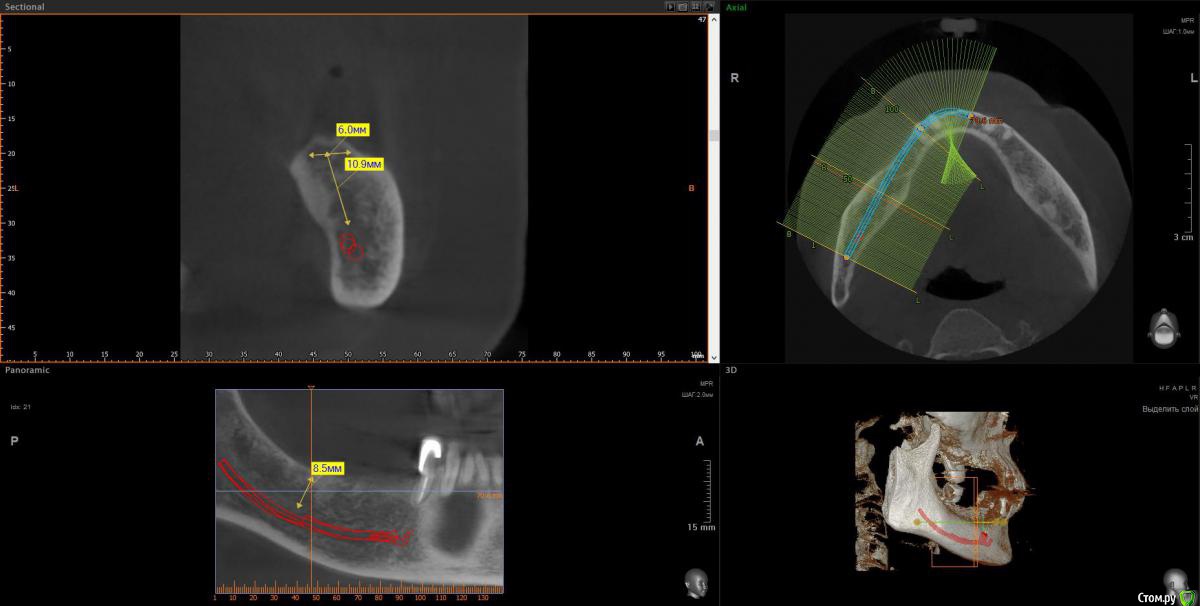

wladdX Опубликовано 11 апреля, 2018 Поделиться Опубликовано 11 апреля, 2018 (изменено) 3-й квадрант Изменено 11 апреля, 2018 пользователем wladdX 1 Ссылка на комментарий

Bier Опубликовано 11 апреля, 2018 Поделиться Опубликовано 11 апреля, 2018 ну да, последний зуб слева я бы удалил. итого 4 имплантата, синуслифтинг на в/челюсти после санации пазухи. 3 Ссылка на комментарий